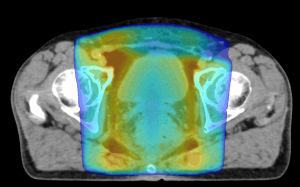

(3)強度変調放射線治療:IMRT(Intensity Modulated Radiaton Therapy)

最新の技術を用いて病巣へ必要な線量を照射しながら、照射範囲近くの正常臓器への線量を通常の照射よりも減らします。それによって高い治療効果と副作用の低減が期待できます。最新機器の導入によりIMRTをより発展させたVMATで治療時間を短縮し、前立腺や頭頚部以外に肺や腹部など全身の病巣に応用しています。